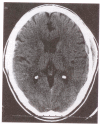

A case of isolated cryptococcal skull infection is presented in a patient with unexplained CD4 lymphopenia and chronic hepatitis B. All cases of this disease reported in the English literature from 1956 to the present are reviewed. The literature suggests that skeletal cryptococcosis is manifested in only 5% to 10% of recognized cases of disseminated cryptococcosis and that isolated skeletal disease without evidence of other tissue involvement is even less common. When isolated bony disease does occur it tends to occur in immunocompromised hosts, particularly those with defects of cell mediated immunity. Any bony site can be involved, most commonly the vertebrae, with the presentation often being a soft tissue swelling and pain in the affected area. Systemic constitutional symptoms occur in a minority of patients. Radiographic investigations are nonspecific and the gold standard of diagnosis remains culture isolation from bone tissue. The most commonly employed therapy for isolated bone disease is amphotericin alone or combined with surgical debridement. The new azoles may have a role in future therapy.